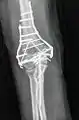

تصوير شعاعي جانبي لمفصل الكوع الأيمن.

تصوير شعاعي لمفصل الكوع الأيمن: قطع عظم.

جراحة إعادة تثبيت عظام الساعد.